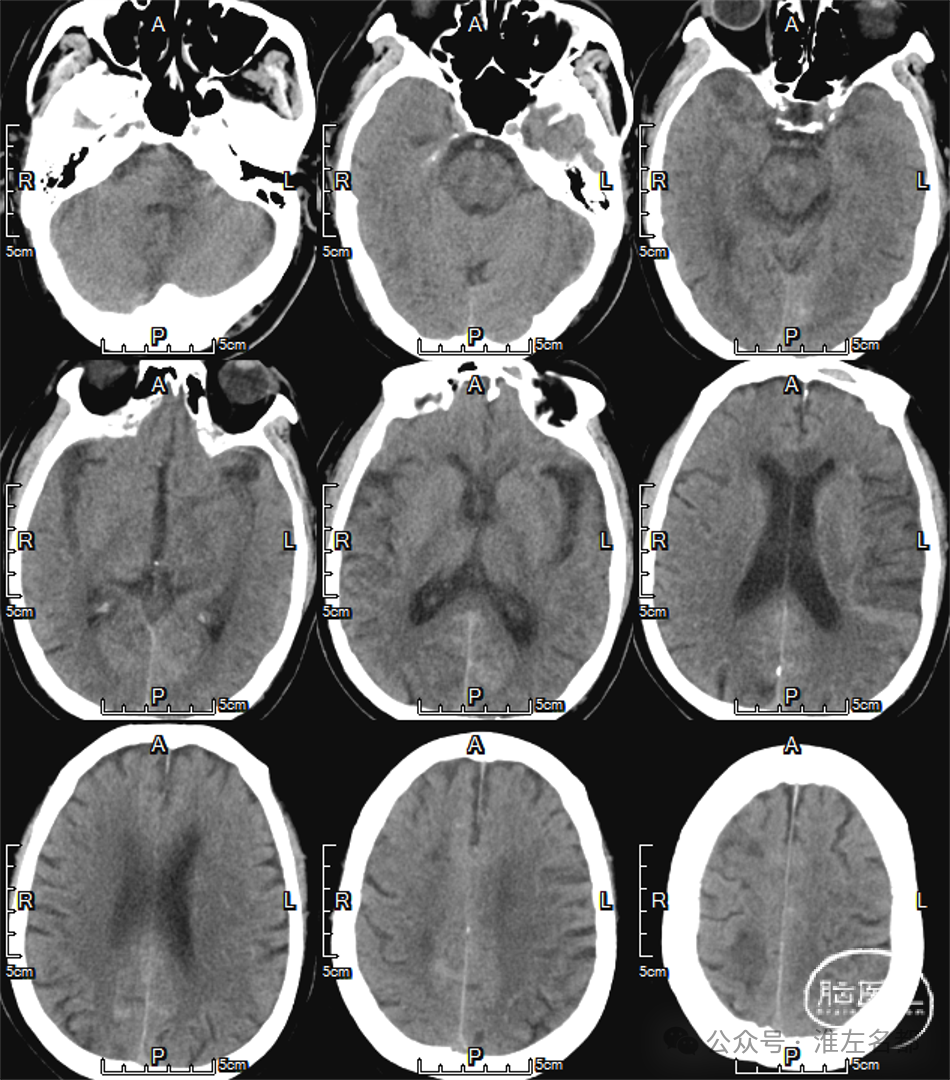

急诊多模式CT

CT平扫:未及明确异常。

颅脑CTA:右侧大脑前动脉A2段局部管腔严重狭窄,右侧大脑前动脉A1段未发育,左侧大脑前动脉A1段粗大。

颈部CTA:所见脑供血动脉未见明确异常。

脑CTP:右侧大脑前动脉供血区局部TTP延长,相应区域CBF和CBV未见明显异常。

2024-01-14 08:36

复查多模式CT

CT平扫:双侧胼体膝部和右侧额顶叶皮质多发梗死低密度影。

CTA:右侧大脑前动脉原A2段狭窄位置管腔闭塞。

脑CTP:右侧大脑前动脉供血区较大范围TTP显著延长。